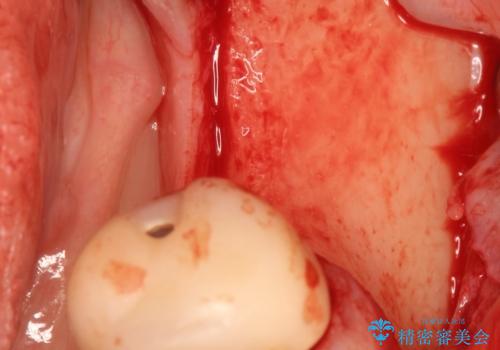

- 左下6番目の歯が欠損しており、インプラントで治療することとなりました。

骨の横幅が薄くなっており、インプラントを埋入するには骨幅が足りない状態でした。

まず最初に骨造成を行い、その後にインプラント埋入手術を行うこととなりました。

骨を増やすための手術が必要になるので、通常のインプラント治療より手術回数が一回多くなってしまうのがデメリットですが、将来的に安定したインプラントにするため、骨造成手術を前もって行いました。

しっかりとした骨幅を獲得し、理想的な太さのインプラントを埋入することができました。